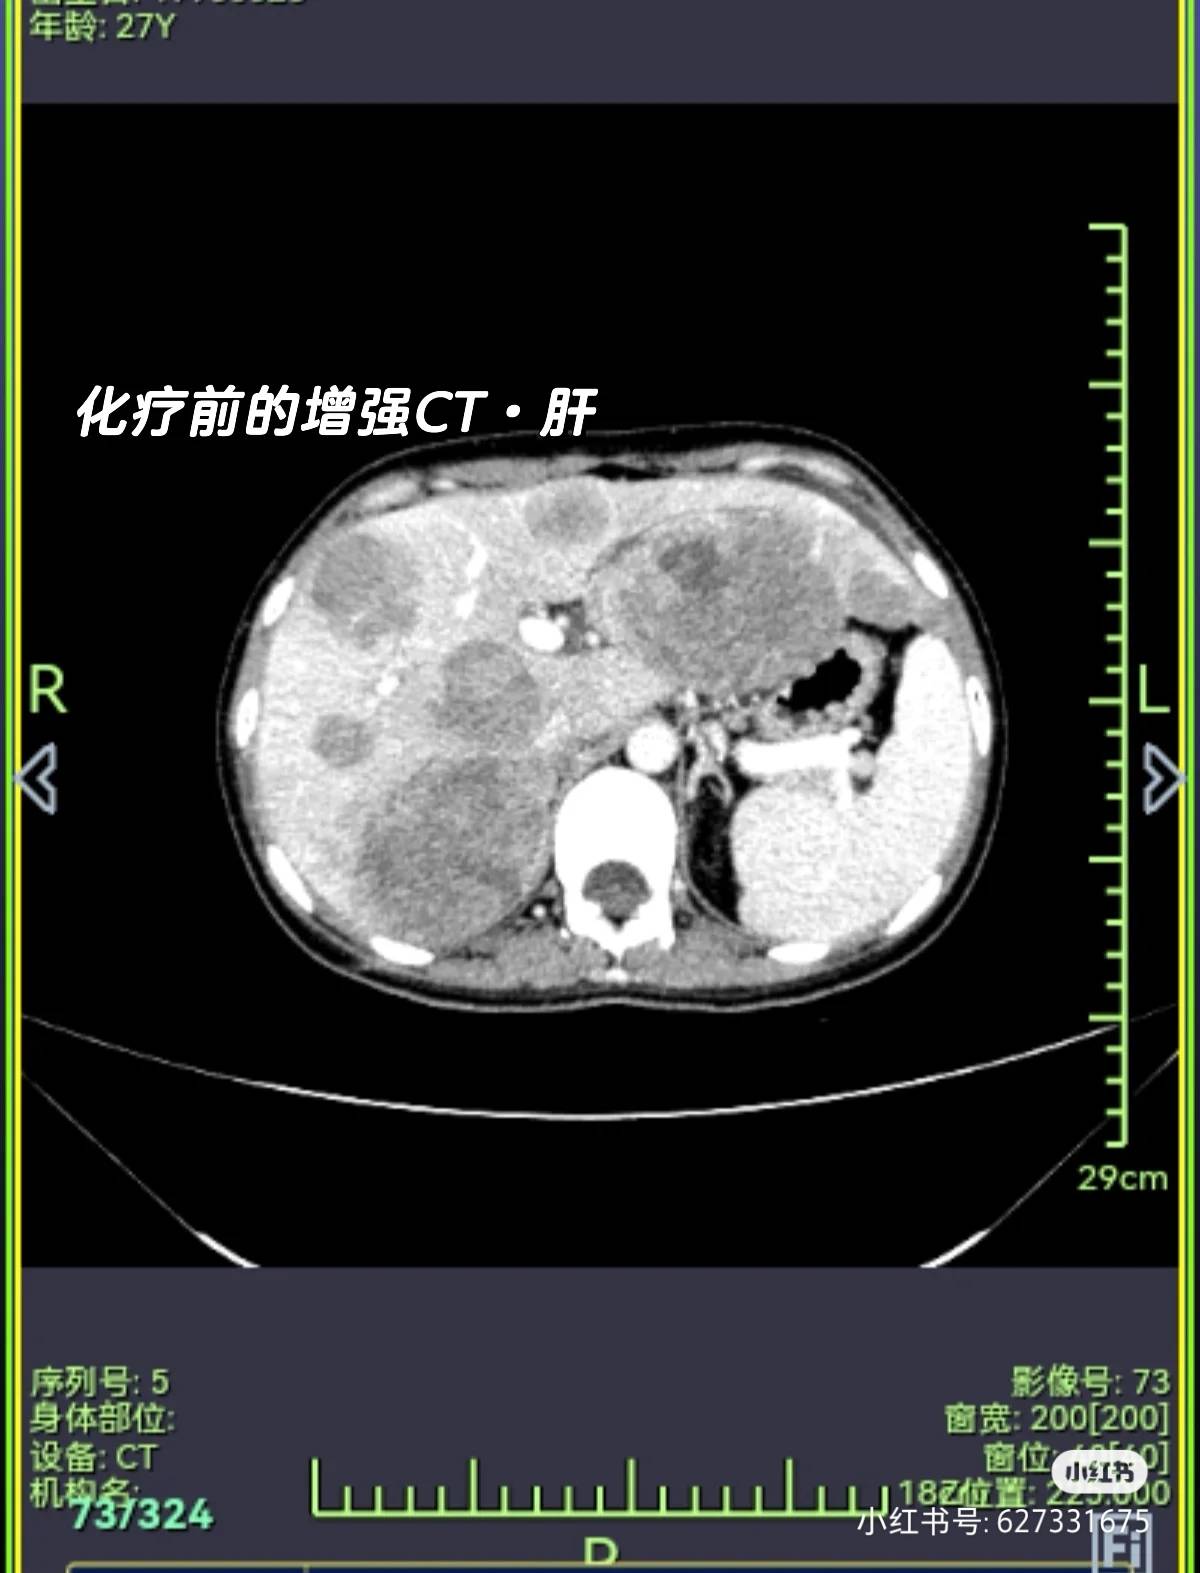

又差不多一个月的时间,感觉上腹部胀痛,腰痛……查出肝转 骨转,医生说只能先化疗了,培美曲塞+贝伐珠单抗+卡铂